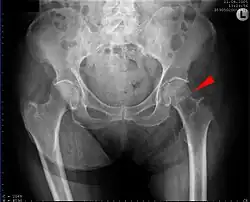

Hip fracture

| Hip fracture | |

|---|---|

| Other names | Proximal femur fracture;[1] femoral neck fracture [main hyponym]; femoral head fracture [other hyponym] |

![]() | |

| Intertrochanteric hip fracture in a 17-year-old male | |

| Symptoms | Pain around the hip particularly with movement, shortening of the leg[2] |

| Types | Intracapsular, extracapsular (intertrochanteric, subtrochanteric, greater trochanteric, lesser trochanteric)[1] |